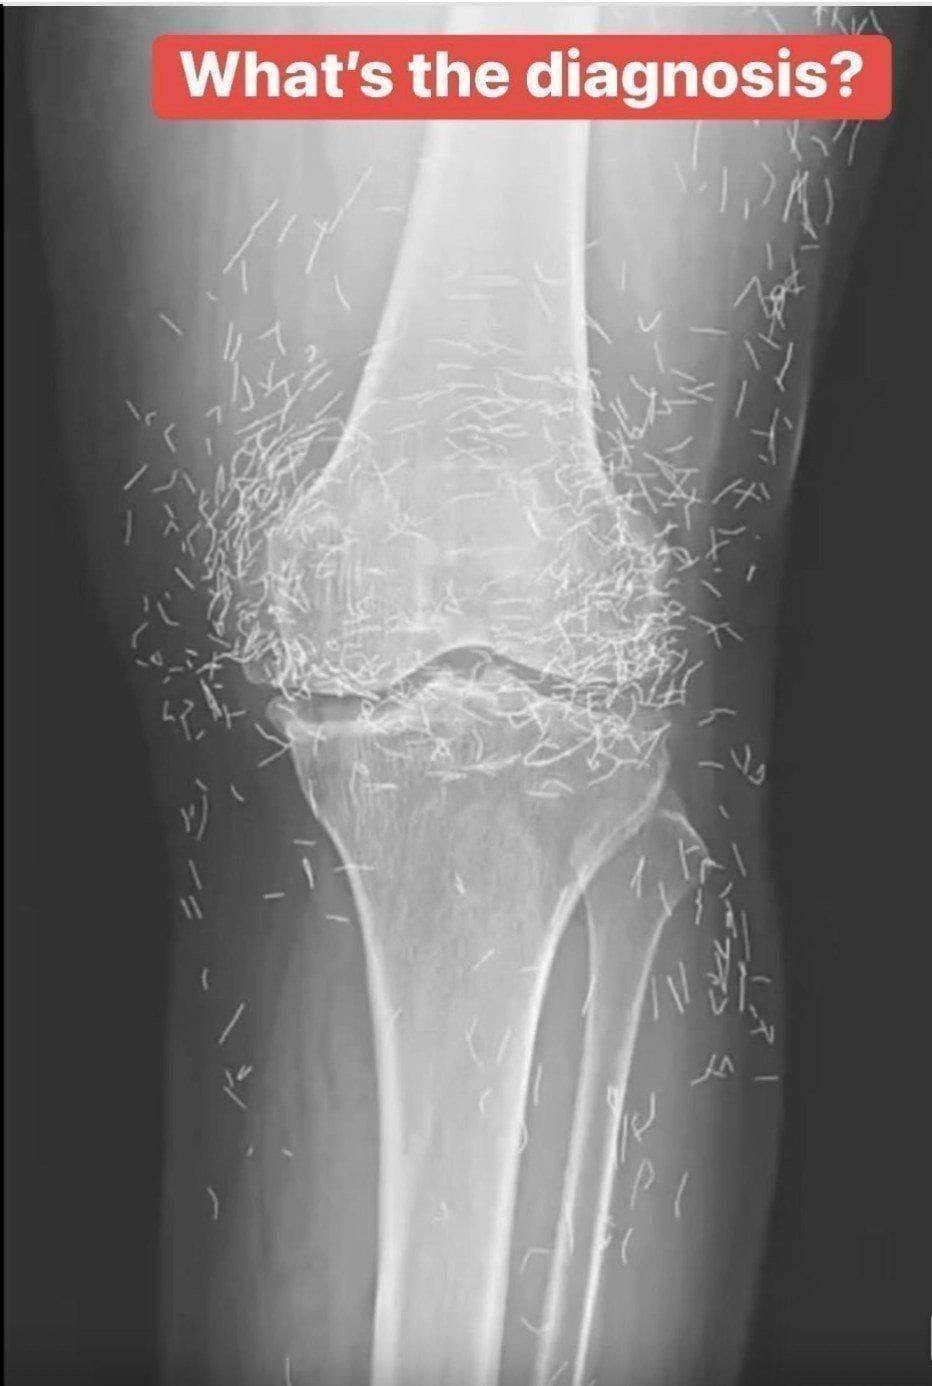

In her case, the needles — believed to be made of gold — were intentionally left inside her knees.

Years later, when doctors took X-rays to evaluate her knee condition, they weren’t prepared for what appeared on the images. Her knees were filled with dozens of bright, metallic flecks — tiny needles embedded deep within the joint area.

The findings were later documented in a case published by the New England Journal of Medicine.

Beyond inflammation, the needles created another problem: imaging complications. Metal objects can obscure parts of the anatomy on X-rays, making it harder for doctors to clearly assess joint damage or disease progression.